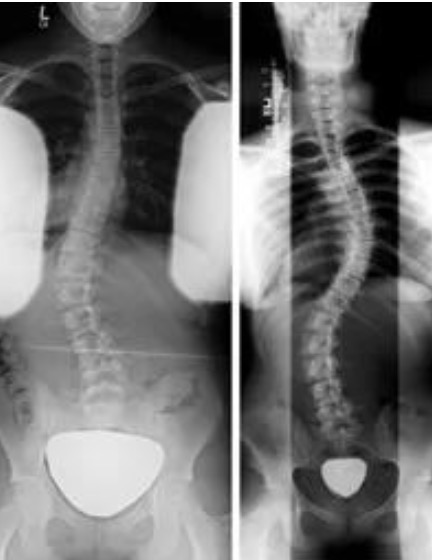

多达25%的人有脊柱侧弯,但最严重的形式只影响约3%

医学专家倾向于等到脊柱弯曲超过10度后才诊断脊柱侧弯。脊柱偏离10度是不容易检测到的,女孩,特别是青春期前的女孩,比男孩更容易发生脊柱侧弯。通常在9年级以下的学生,任何积极的发现都会直接报告给家长。医生也可以为孩子筛查,如果及早发现并采取纠正训练,即使不能治愈,也可以控制脊柱侧弯的影响。.....